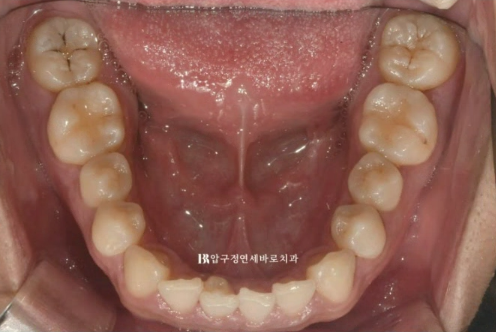

아래 앞니 하나가 삐뚤합니다.

특히 아래 앞니 중 하나에 기형치도 보입니다.

뒤쪽으로 튀어나온 부분은 치아의 일부 입니다.